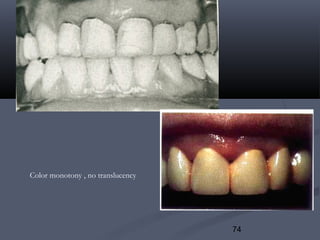

7.Color monotony7.Color monotony:: the tooth appears as if it is made ofthe tooth appears as if it is made of

dentine only.dentine only.

Lack of translucency:Lack of translucency:

Color monotony , no translucency